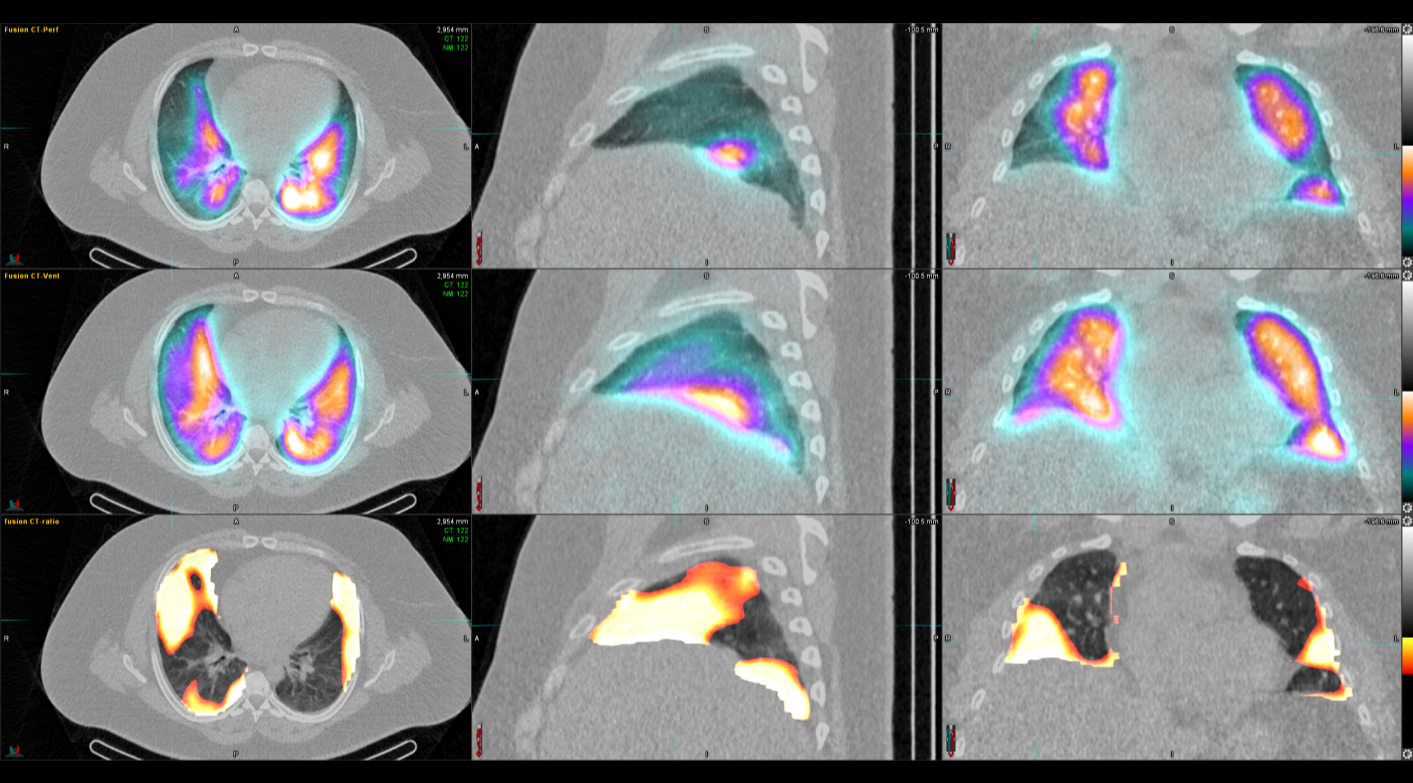

Όλες οι μελέτες Πυρηνικής Ιατρικής πραγματοποιούνται με SPECT/CT μέθοδο στις 2 υπερσύγχρονες SIEMENS Pro SPecta. Από το δυσδιάστατο στο τρισδιάστατο, από την υπόνοια στη βεβαιότητα.

Οι μελέτες μυοκαρδίου πραγματοποιούνται με τη χρήση της μοναδικής τεχνολογίας IQ SPECT που εξασφαλίζει μικρό χρόνο απεικόνισης – μικρή δόση – υψηλή διακριτική ικανότητα/ανάλυση.